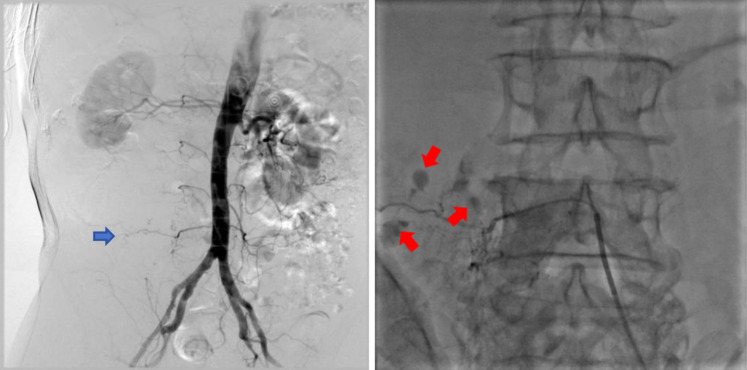

Transcatheter arterial embolization for retroperitoneal bleeding in patients with lumbar artery injury and essential thrombocythemia: a case description.